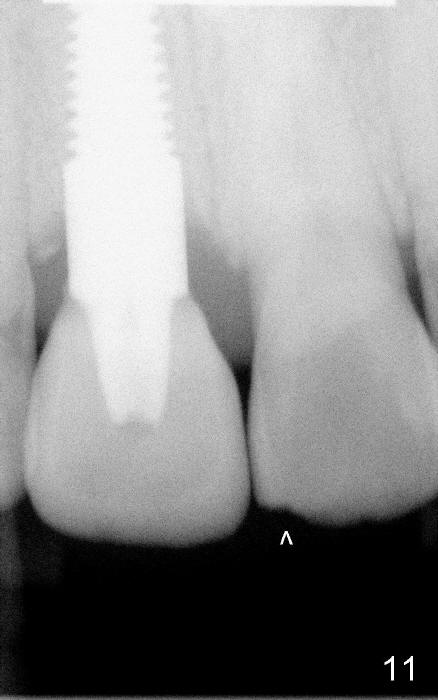

Fig.11,12 are taken 6,18 months post cementation, respectively.